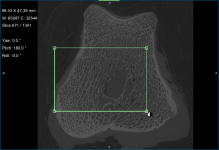

- Create a box that either entirely or partially encloses the region of interest as follows:

- Click the Box button in the Shapes panel.

A new Box shape appears in the Data Properties and Settings panel. Click the Eye icon to show the box in the workspace views.

- Adjust the box in the 2D and/or 3D views of the region of interest, as required.

You can resize and rotate the box, as well as change its position with the available control points (see Editing Shapes).